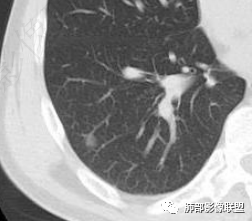

右下叶胸膜下结节,轻分叶,结节内可见低密度区,CT值一83Hu,结节周围见空气新月征(黑边征),结节膨胀性生长,收缩力差,轻度强化,体检发现,综合分析,考虑错构瘤,但多个层面显示结节周围有边缘清楚的磨玻璃影,不知是否与层厚有关,有似清非清的感受,鉴别排除一下低分化腺癌

感觉磨玻璃影是容积效应

看到视频,是容积效应

那错构瘤的可能性就较大了

此病例中结节,与支气管无关系,边缘清晰,形态规则,缺乏张力,未见典型的分叶及毛刺,病灶周围磨玻璃为部分容积效应所致,肺门纵隔未见肿大淋巴结,良性病变可能性较大,肺部的良性肿瘤中,最常见的是错构瘤,其次是硬化性肺细胞瘤(PSP),第三是孤立性纤维性肿瘤(SFT)。

常表面光滑,可有浅分叶或无分叶,无毛刺,对周围肺组织无牵拉;常挂枝头(挂在肺动脉枝头上),很少到达胸膜。出现脂肪成分,或者典型的爆米花样钙化几乎可以确诊,软骨型错构瘤因软骨组织多,强化弱。平滑肌型错构瘤增强有一定强化。病灶周围边界清楚,常有很低密度的黑晕。